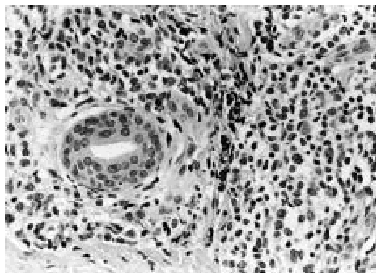

Se realizó una biopsia de la lesión cutánea (fig. 2), que demostró una infiltración perivascular superficial y profunda y perianexial por grupos de células grandes con gran desproporción núcleo-citoplasmática, citoplasma amplio eosinofílico y núcleo irregular con nucléolo prominente (fig. 3), siendo sugestiva de infiltración por LMA.

Fig. 3.--Detalle en el que se identifican claramente las células mieloides atípicas, con núcleos pleomórficos y nucléolos evidentes, rodeando un conducto sudoríparo.

Histopatológicamente7, 11, 12 muestran un denso infiltrado granulocítico dérmico de intensidad variable, de distribución difusa o nodular, preferentemente perivascular y perianexial, que ocasionalmente invade el tejido celular subcutáneo. El infiltrado característicamente respeta la parte alta de la dermis papilar. Las células neoplásicas son de gran tamaño, con citoplasma abundante y núcleo oval o indentado, que contiene uno o varios nucléolos. En el caso de la LMA M29, que es la que presenta nuestro paciente, predominan las células mononucleares de mediano o gran tamaño, con citoplasmas escasos y núcleos basófilos excéntricos con nucléolos evidentes (mielocitos y mieloblastos atípicos). Las técnicas de inmunohistoquímica pueden ser utilizadas para confirmar la naturaleza del infiltrado leucémico13. La mayoría de las células leucémicas de la LMA tiñen fuertemente su citoplasma con lisozima y CD43. Las células neoplásicas bien diferenciadas son positivas con cloroacetato esterasa y alfa-1 antitripsina7.